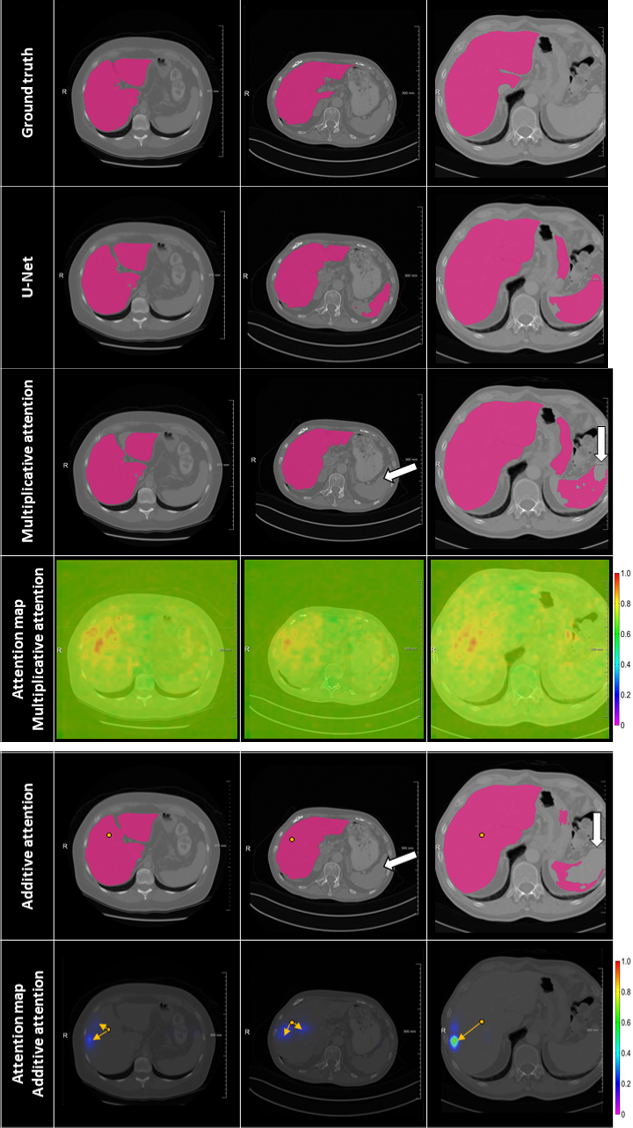

My major research project at Quantib, Rotterdam.

Purpose: To support doctors in diagnosis and treatment planning of liver tumors, there is a growing demand in the clinical practice for an accurate and automatic liver and tumor segmentation method. Recent developments of deep learning models, have caused these models to be very often used for automatic segmentation tasks. This study investigates the influence of additive and multiplicative self-attention on the automatic liver segmentation performance of U-Net.